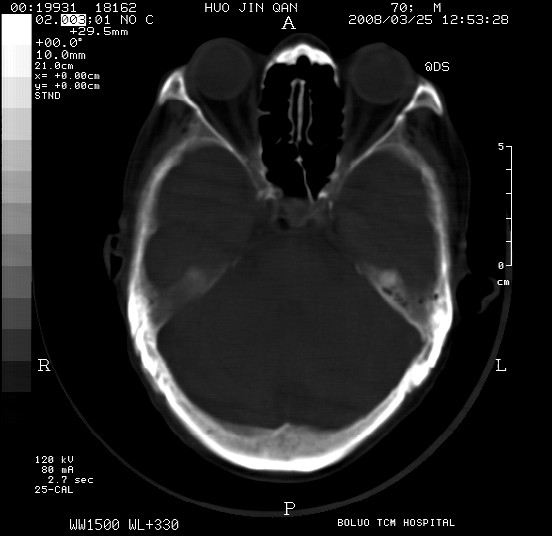

以下是引用随光逐影在2008-3-25 20:15:00的发言:[br]双侧额颞顶部亚急性(或慢性)硬膜下血肿。

以下是引用liuyue在2008-3-26 18:57:00的发言:[br]以下是引用随光逐影在2008-3-25 20:15:00的发言:[br]双侧额颞顶部亚急性(或慢性)硬膜下血肿。 [br]支持![br]可以无明显外伤病史,老年人可以在激烈摇晃或轻微头部碰创头部时,发生硬膜下出血.